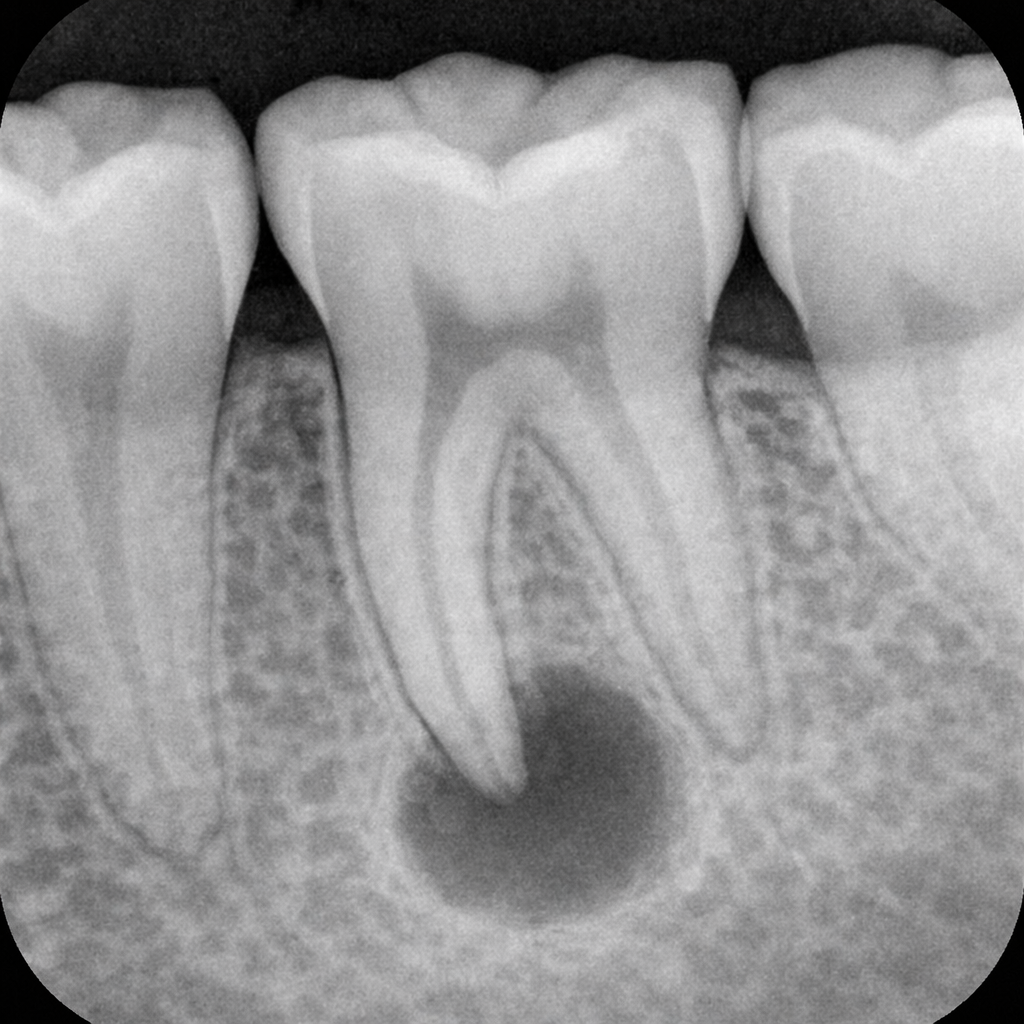

• 발치 즉시 식립 시, 1mm 이상의 안면측 치은 퇴축(Recession) 발생 빈도가 중윗값 26%에 달하는 것으로 나타났습니다.

• 즉시 식립 시 골 이식을 동반하더라도 36~57%의 사례에서는 CBCT상 협측 골벽이 관찰되지 않았으며, 이는 치은 퇴축의 주요 원인이 됩니다.

충분한 잔존 치조골량

임플란트가 튼튼하게 고정되기 위해서는 발치(치아가 빠진 구멍) 주변에 3~5mm 이상의 건강한 뼈가 남아있어야 합니다. 이는 초기 고정력을 확보하기 위한 물리적인 최소 조건입니다. 뼈의 양이 부족하다면 즉시 식립보다는 뼈 이식 후 시간을 두는 지연 식립이 더 안전합니다.